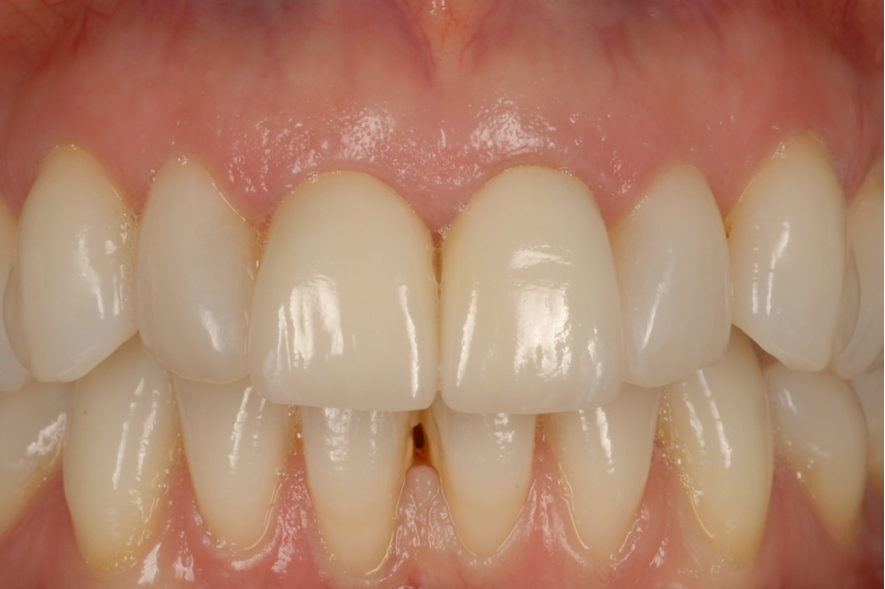

An example of one of the first cases that we did this way is below, including the most recent images of the case.

This illustrates the power of guided surgery and constant improvement.

Here is a more recent case…

Not only have we honed our techniques and are using the better, modern equipment available to us, but our systems and processes allow us to work smarter, not harder.